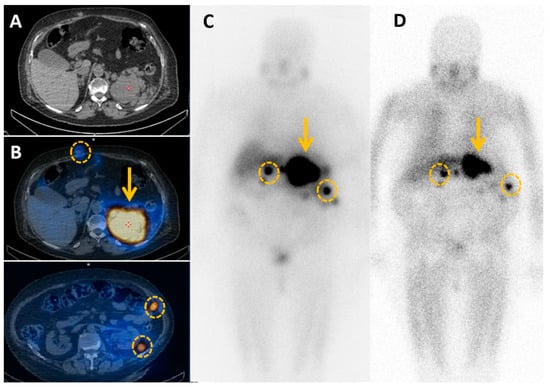

4.2. Contributions of Computed Tomography Using Dopamine and Glucose Analogues

4.3. Positron Emission Tomography with Computed Tomography Using Somatostatin Analogues